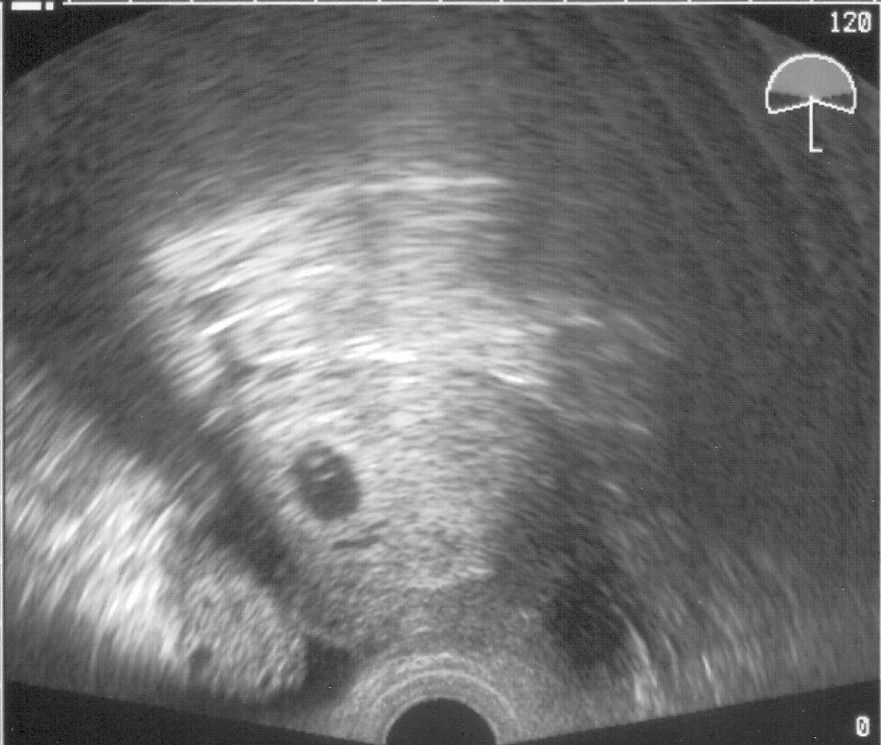

melde mich gehorsamst aus England zurück, haben alles gut überstanden. Waren gestern nochmal beim US und haben Euch was zum Mutmachen mitgebracht (s.u.)

US 2007-11-01 - 5+6 klein.jpg

KatZ-LE Meinen Glückwunsch!! *knuddel* Hoffentlich können wir hier bald auch alle so ein schönes US-Bildchen vorweisen! :knuddel:

sorry, tue mich noch schwer mit der Technik. Keine Ahnung wie KatZ-Le sogar ein US-Foto von der Qualität hier reinbringt :oops: